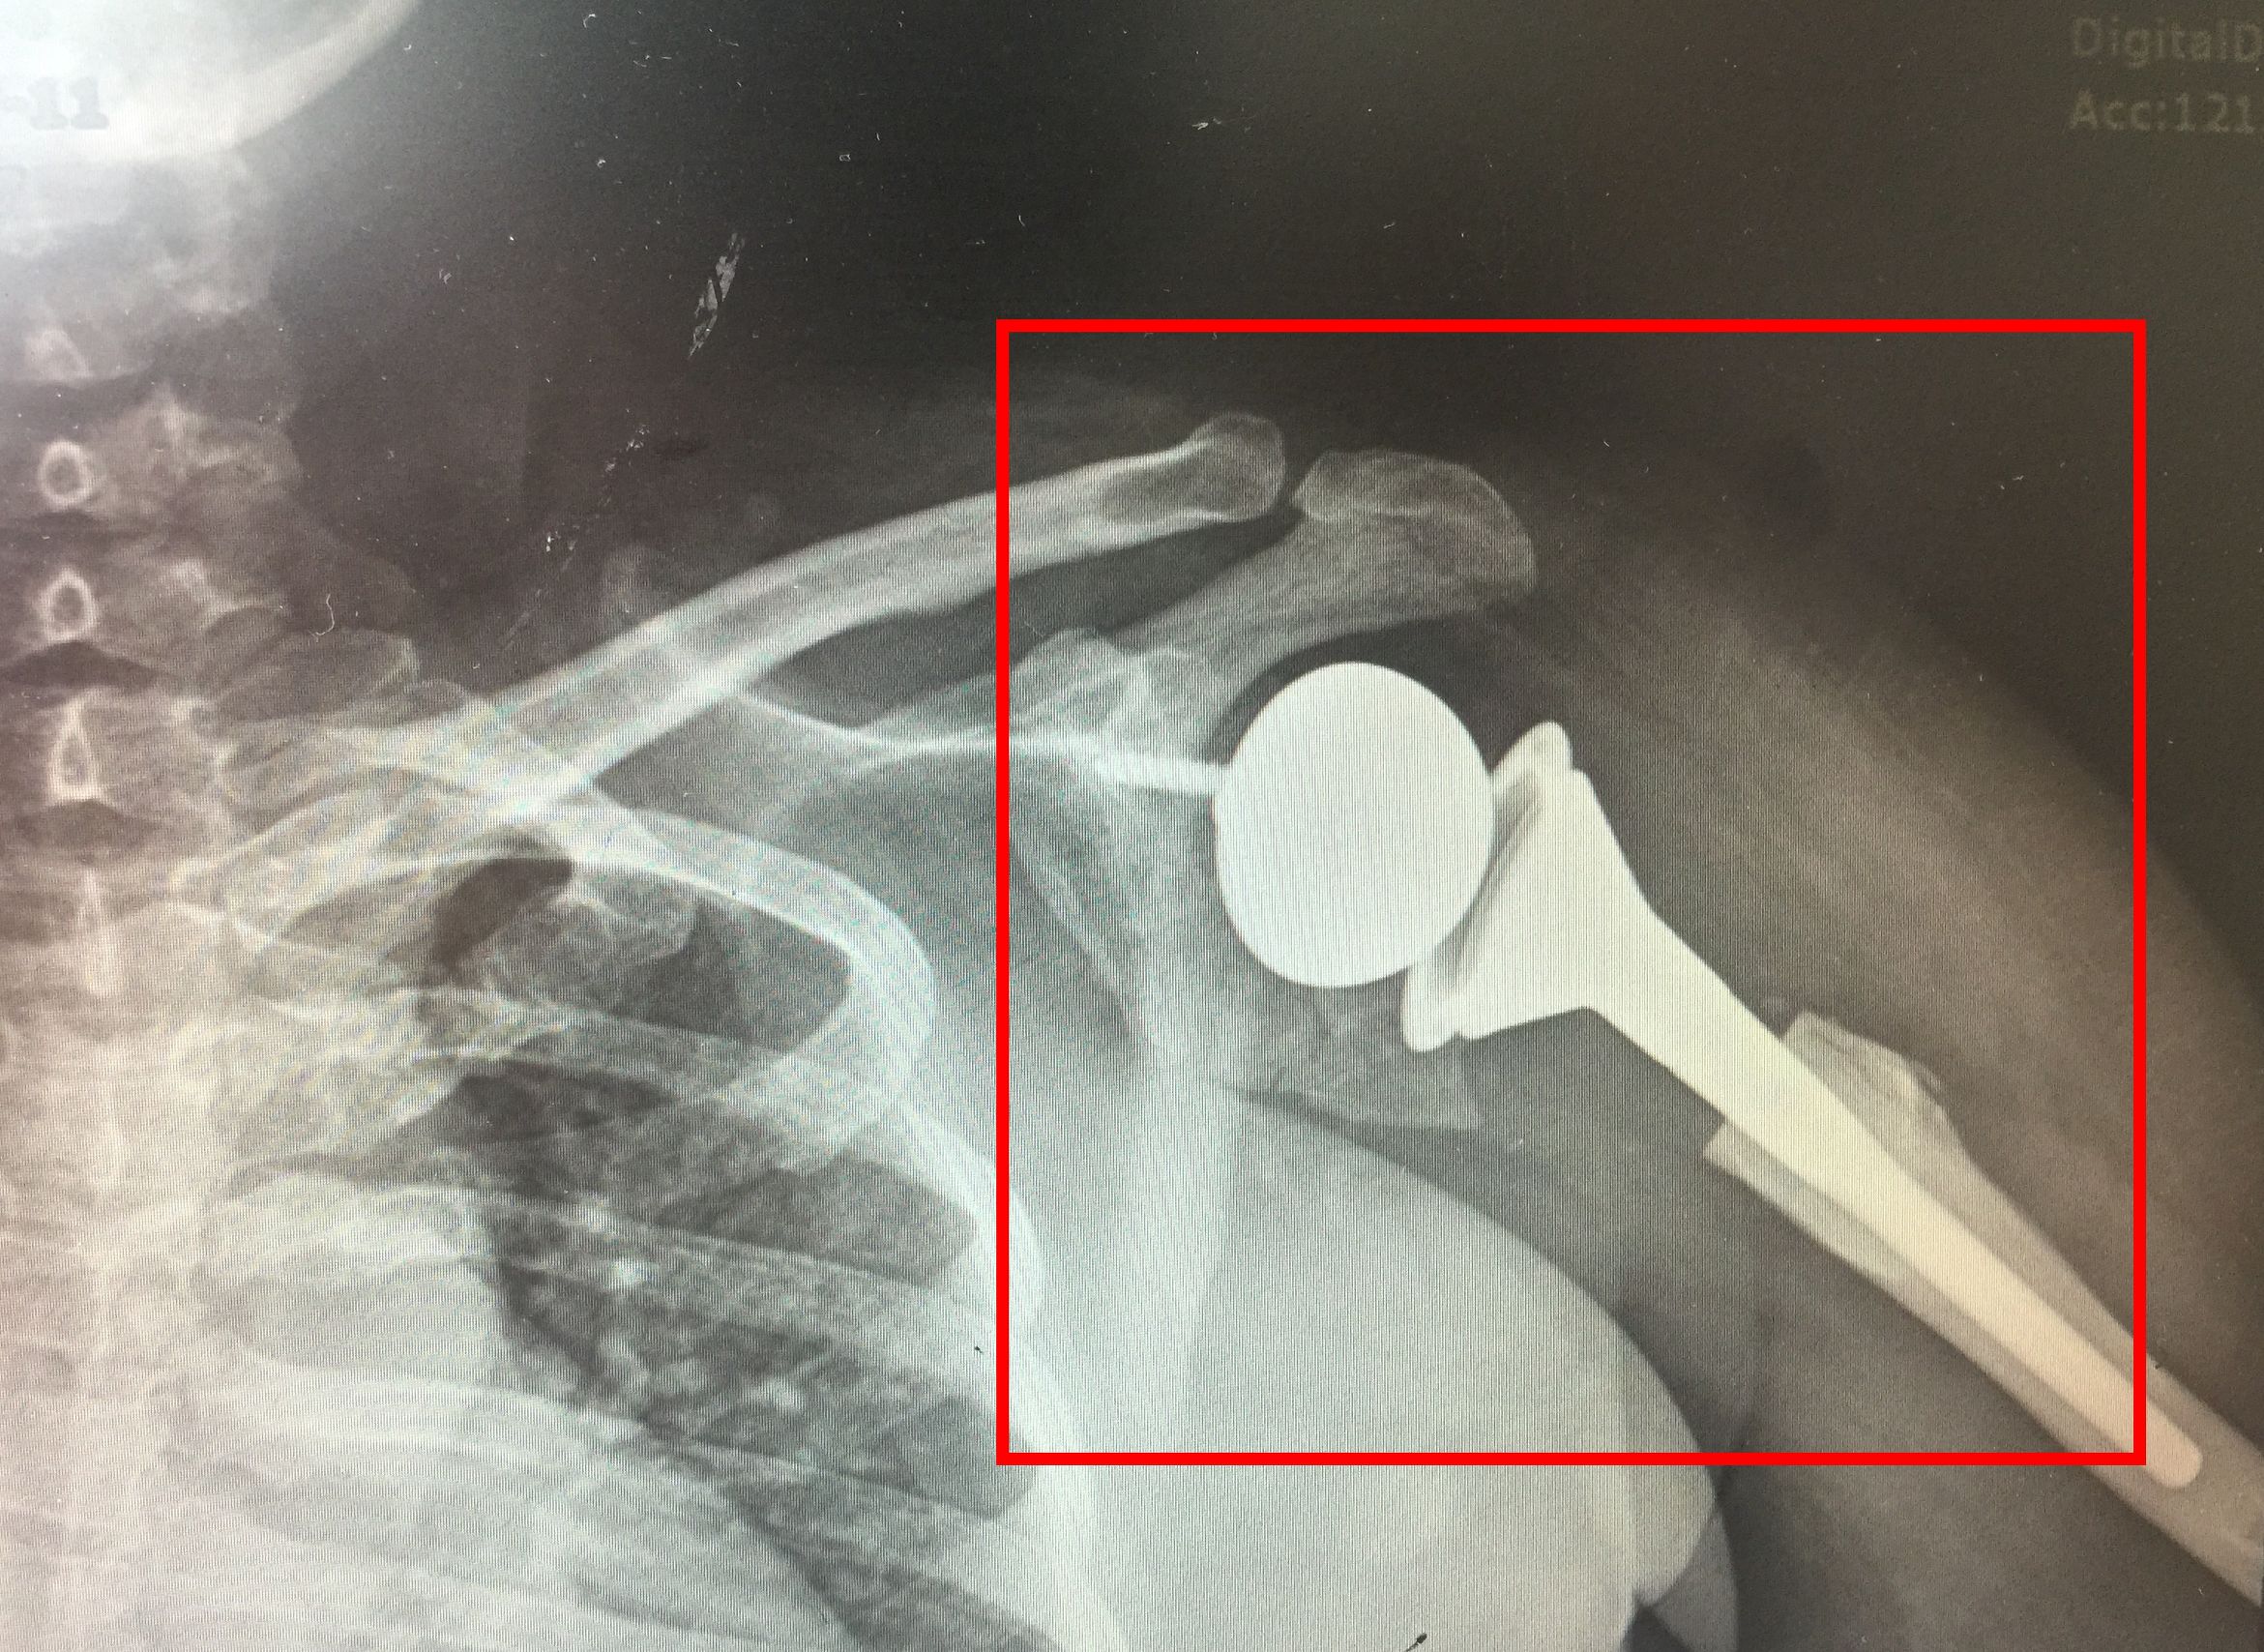

患者的X光片让接诊的关节外科主任曹国平吃了一惊!童阿姨的左侧肱骨头已经全部坏死,只剩下一个空壳,肩关节盂缺损明显导致肩关节严重脱位、周围组织结构异常、肩袖缺失,必须进行关节置换手术才有可能恢复肩关节功能。“但是因为她情况比较特殊,肱骨头已经基本上没有了,再加上肩袖缺失,如果采取一般的肩关节置换手术,关节活动度不佳、易脱位。”曹国平介绍说,“所以这次我们需要进行一次开创性的手术。”

曹国平说的这项开创性手术就是反置式人工肩关节手术。该项技术是目前世界较高层次的医疗手术,操作技术与难度都很大,而且在省级医院也开展得比较少。为确保手术成功,曹国平团队在术前进行了CT、磁共振、X光片、计算机三维模拟等一系列准备,一步步完善手术方案。7月5日,手术顺利完成,从取出坏死的肱骨头到完成所有假体的安装置换,仅用了1个多小时。该手术的成功,填补了我院在反置式人工肩关节置换技术领域的空白,标志着在肩关节置换技术上又达到了一个新的高度。

术后置换好的假体

术后童阿姨状况良好,手术当天晚上即可开始活动上肢,肩关节假体位置良好,现在已经康复出院。